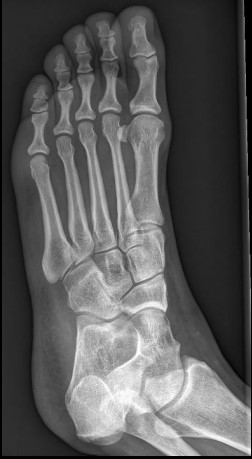

Il s'est choppé le pied